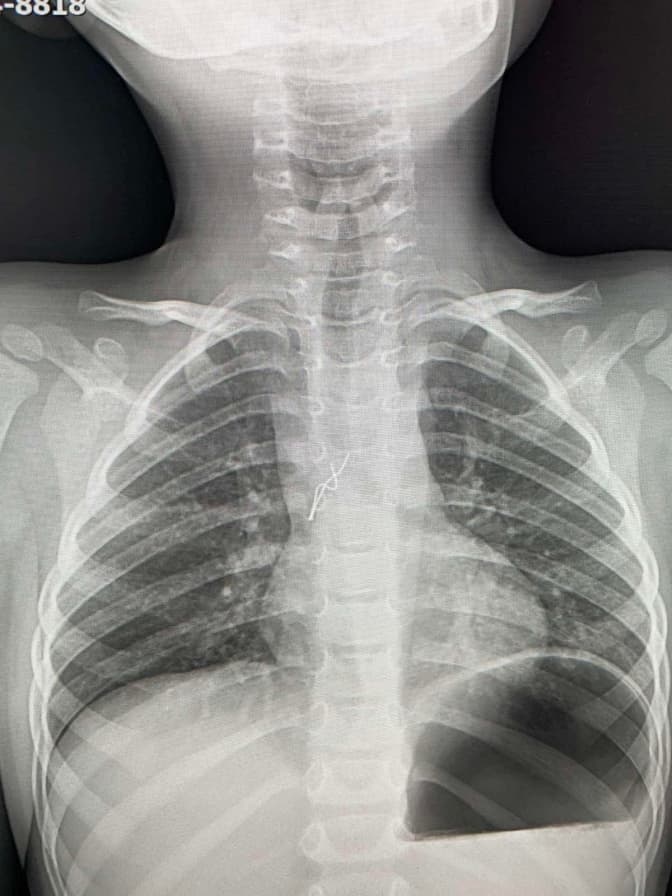

Чергові лікарі зробили рентгтен і побачили стороннє тіло у дихальних шляхах. Вуса лампочки травмували слизову оболонку дитини в ділянці біфуркації трахеї, там уже утворилися дрібні крововиливи. Діставали гірлянду без жодного розрізу за допомогою бронхоскопії. Зокрема, вусики гірлянди лікар захопив щипцями, завів їх у тубус бронхоскопа, щоб не травмувати бронхи і трахею під час видалення. Разом з цим тубусом лампочку і дістали.